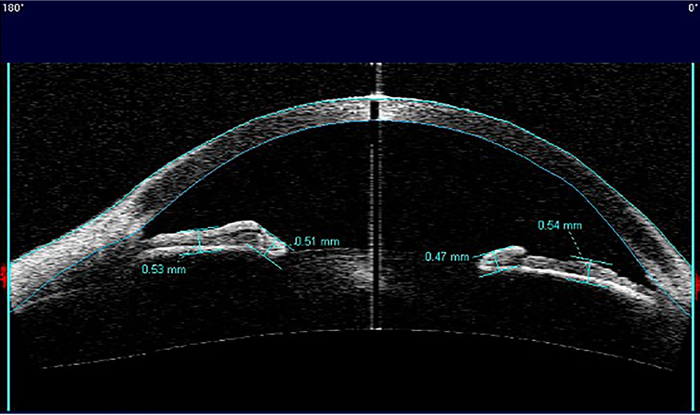

The analysis considered only the images with the scanning acquisition plane set at 180° through the centre of the pupil in order to avoid interference with the lid margin. The investigation examined the iris thickness in 2 different positions for all patients: in the Dilator Muscle Region (DMR) and in the Sphincter Muscle Region (SMR), according to the methodology described by Prata et al. [20]. Briefly, the study considered the pupillary margin as the medial edge and the temporal periphery of the iris as the temporal landmark.

The region of the dilator muscle was measured at half of the distance between the scleral spur and the pupillary margin and the region of the sphincter muscle at 0,75 mm distance from the pupillary margin Fig. (1a-c). For the statistical analysis, we considered the mean value of the measurements calculated at two sides of the pupil.

At the level of the dilator muscle region, the iris thickness significantly reduced in patients with POAG or OHT under treatment with PG compared to both healthy subjects (0,51 mm±0,067 vs. 0,55 mm±0,055; p<0,0001) and patients under treatment with drugs different from PG or alpha-adrenergic agonists (0,51 mm±0,067 vs. 0,56 mm±0,057; p<0,0001) Fig. (2). On the contrary in the region of the sphincter muscle, the values of iris thickness were significantly higher in patients in therapy with PG compared to both control groups (0,59 mm±0,074 vs. 0,52 mm±0,064, healthy controls) (0,59 mm±0,074 vs. 0,52 mm±0,049, patients in therapy with drugs different from PG or alpha-adrenergic agonists) (p<0,0001) Fig. (3). To confirm the intersubject variability, the ratio between DMR and SMR values (DMR/SMR) was also assessed. Significantly lower values were found in the PG group compared to healthy subjects (0,88±0,085 vs. 1,07±0,092; p<0,0001) and to patients in therapy with eyedrops different from PG and alpha-adrenergic agonists (0,88±0,085 vs. 1,07±0,099; p < 0,0001) (Fig. 4).

In particular, Visante OCT scans revealed a significant reduction in iris thickness at the level of the dilator muscle and a significant increase in the region of the sphincter muscle of patients under treatment with prostaglandin analogues compared to both control groups (healthy subjects and patients under treatment with antiglaucoma drops non containing PG or alpha-adrenergic agonists). These alterations seem to be not influenced by age and not related to the length of treatment. Moreover, the study documented a reduction in DMR/SMR ratio in patients with POAG or OHT using PG compared to the other two groups, strengthening the previous findings that indicate a relevant modification of the iris morphology observed only in the PG group.